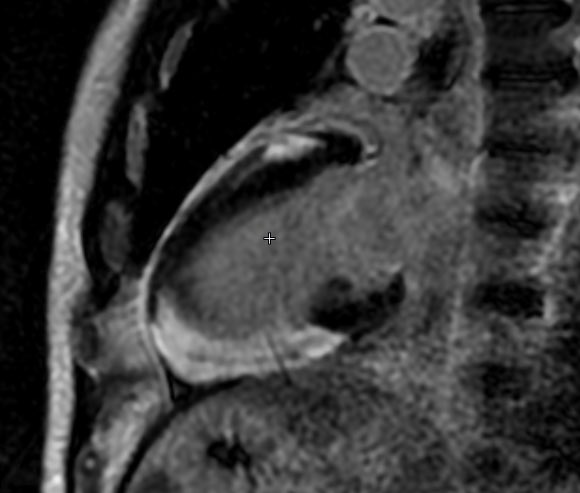

Join us for the SCMR/SISIAC Joint Webinar: “Sarcoidosis – Clinical Images” 🗓️ October 30, 2025 – 1:00 PM EST Discover #CMR findings and best practices for diagnosing cardiac sarcoidosis Register here : https://t.co/YSHSeY6yO9 #SCMR #SISIAC #Sarcoidosis #CardiacMRI #CMReducation